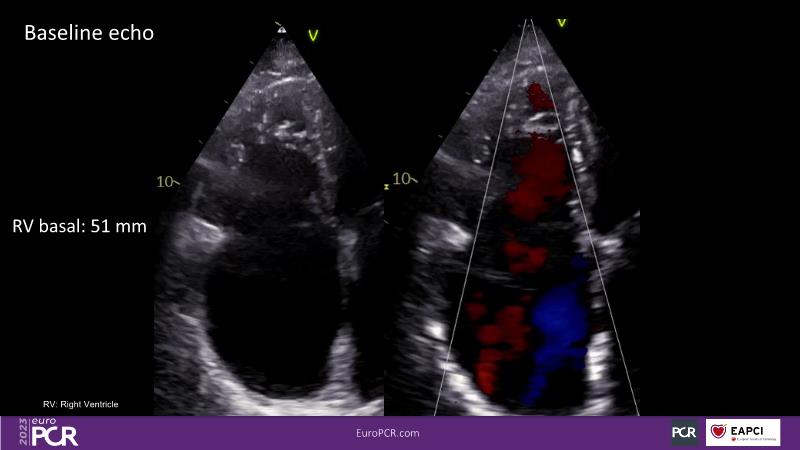

Tailoring tricuspid regurgitation patient treatment with the PASCAL Precision system

- To discuss the different tricuspid regurgitation phenotypes that can be treated with the PASCAL Precision repair system

- To participate in a case-based discussion using the PASCAL Precision repair system for the treatment of tricuspid regurgitation